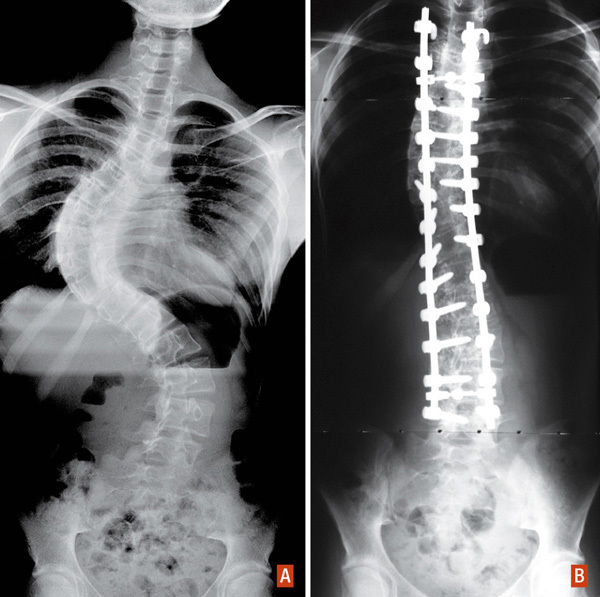

Traitement chirurgical d’une scoliose combinée thoracique droite et lombaire gauche sévère. A : radiographie de face préopératoire. B : radiographie de face postopératoire.